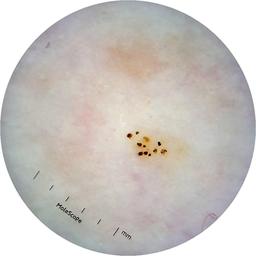

ISIC_6363669

IP_1322385

IL_2591344

acquisition_day 264

age_approx 65

anatom_site_1 Trunk

anatom_site_2 Anterior trunk

anatom_site_general anterior torso

diagnosis_1 Benign

diagnosis_confirm_type single image expert consensus

image_type dermoscopic